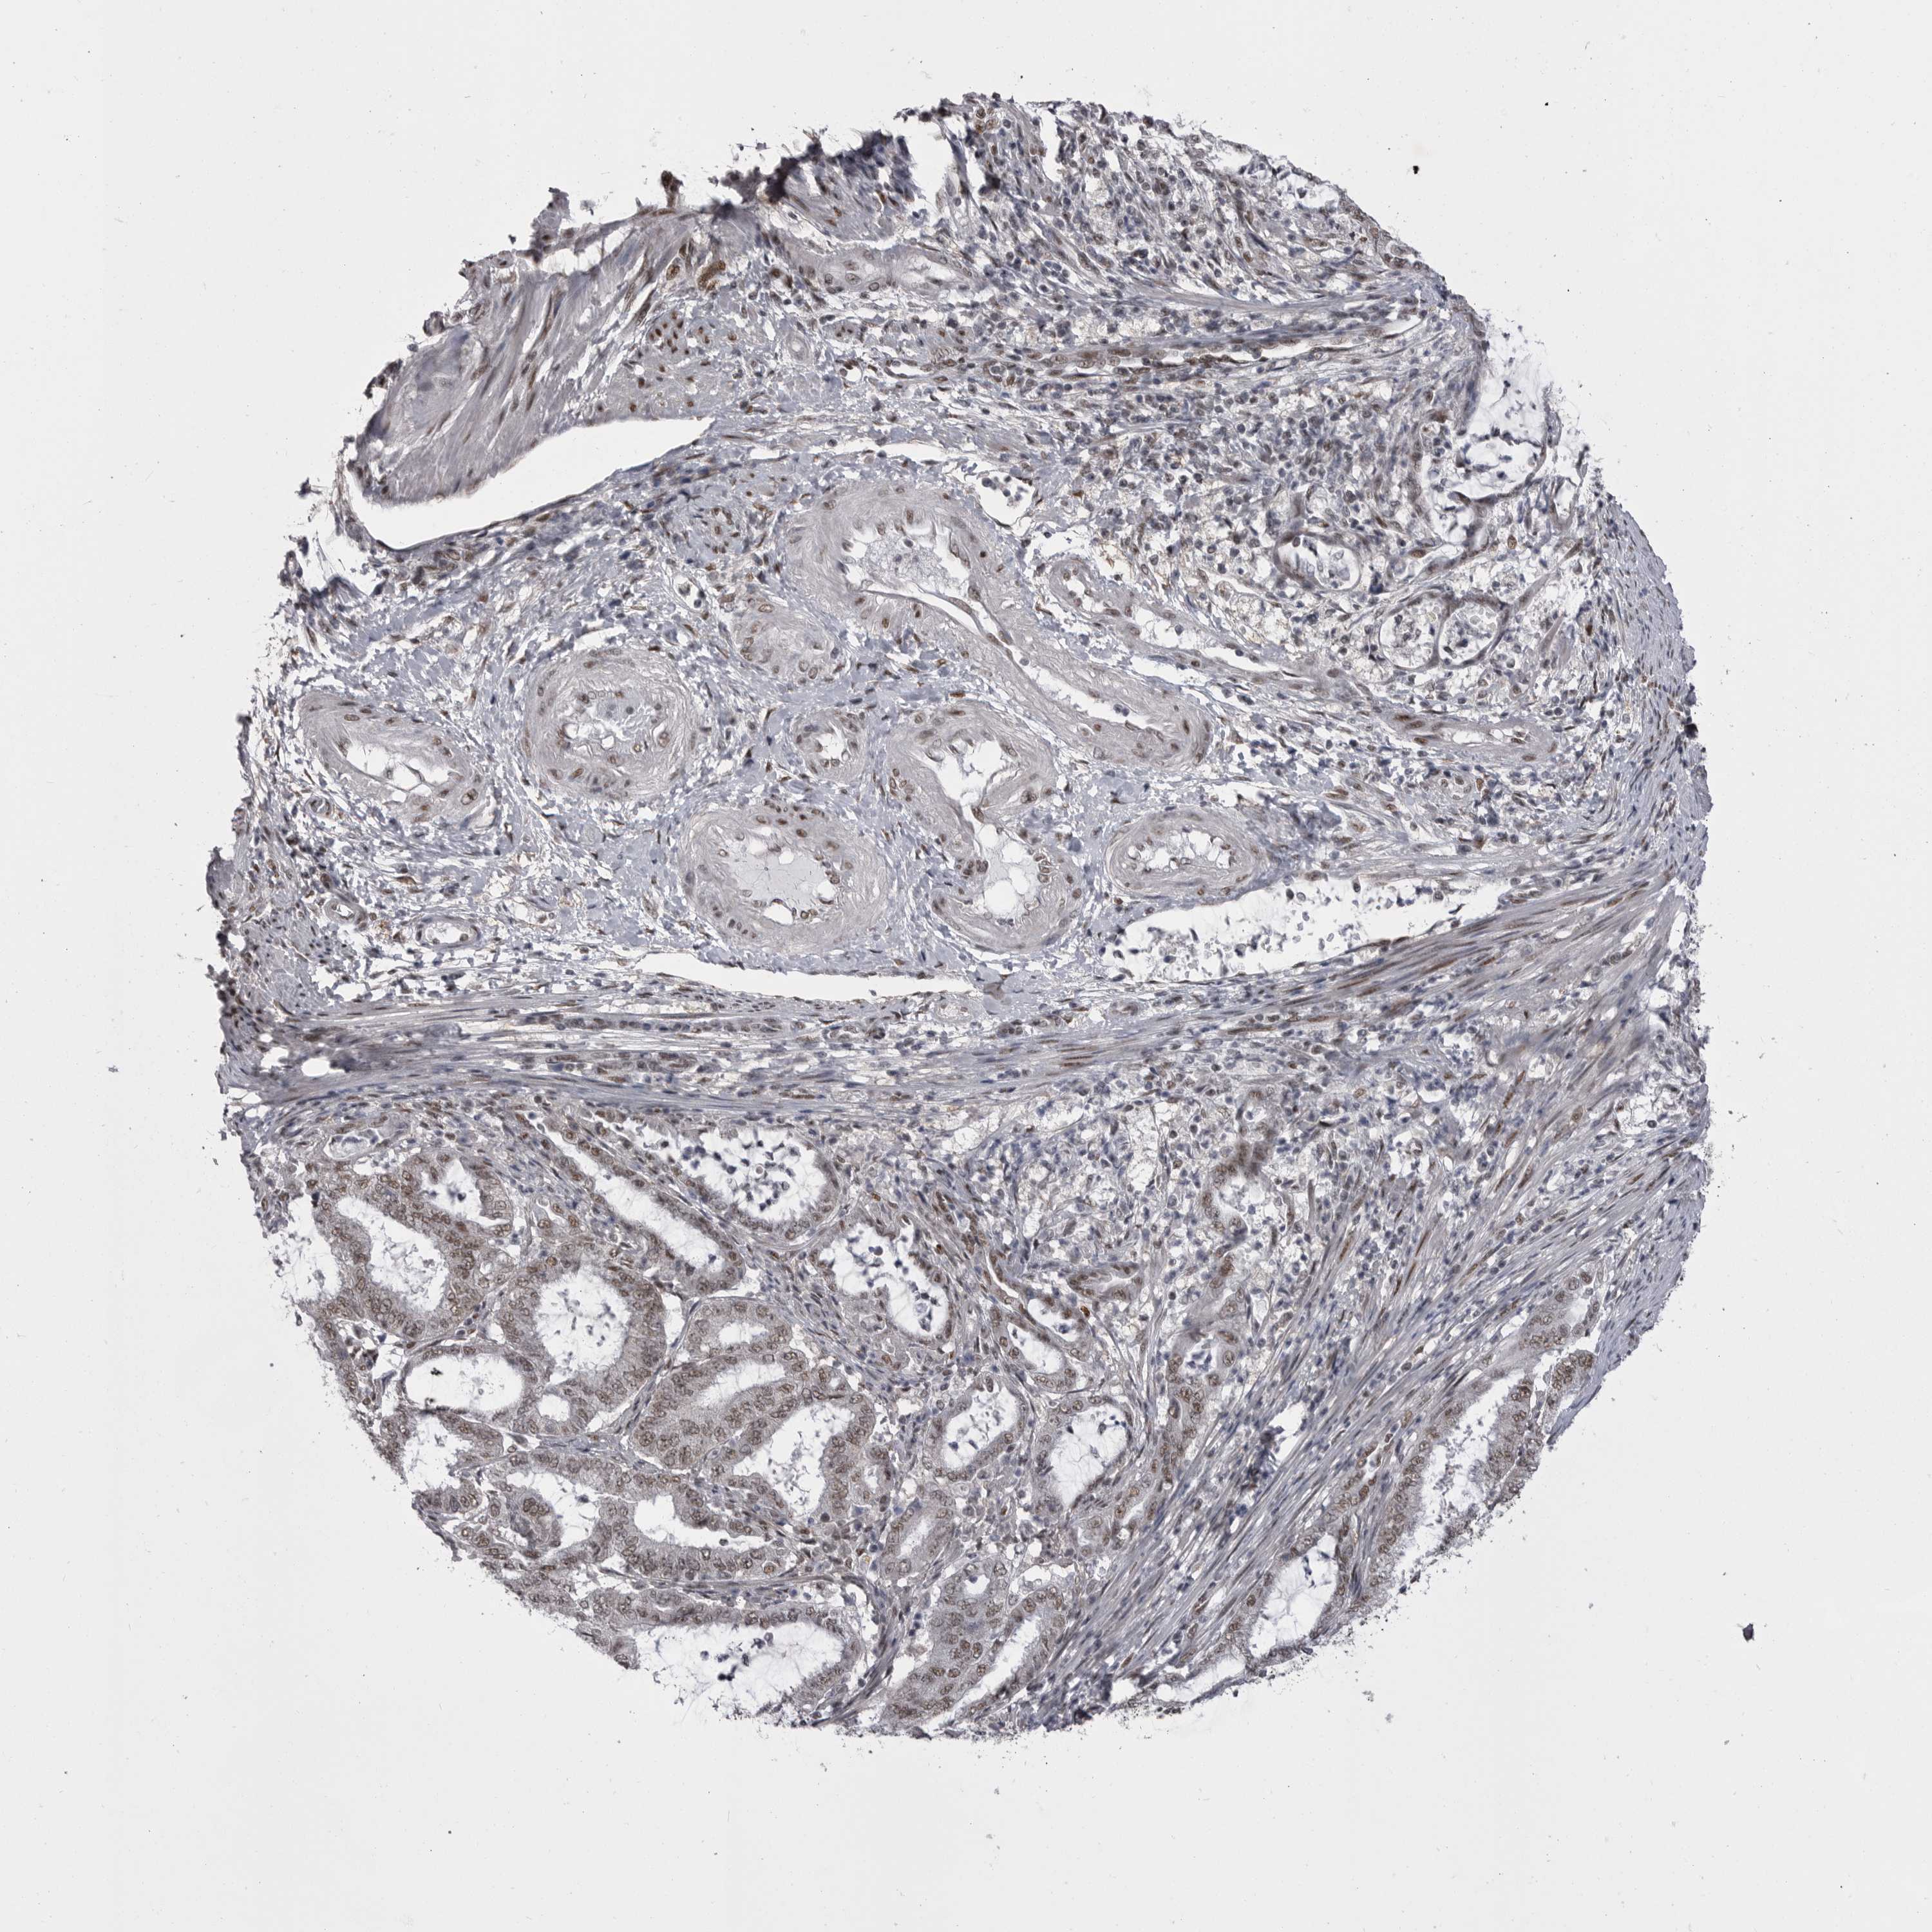

ENDOMETRIAL CANCER - Protein expressioni

A mouse-over function shows sample information and annotation data. Click on an image to view it in a full screen mode. Samples can be filtered based on level of antibody staining by selecting one or several of the following categories: high, medium, low and not detected. The assay and annotation is described here.

Note that samples used for immunohistochemistry by the Human Protein Atlas do not correspond to samples in the TCGA dataset.

Antibody stainingi

Antibody staining in the annotated cell types in the current human tissue is reported as not detected, low, medium, or high, based on conventional immunohistochemistry profiling in selected tissues. This score is based on the combination of the staining intensity and fraction of stained cells.

Each image is clickable and will lead to virtual microscopy that enables deeper exploration of all samples and also displays staining intensity scores, fraction scores and subcellular localization as well as patient and tissue information for each sample.

Antibody HPA051587

Antibody CAB026384

Staining

High

Medium

Low

Not detected

Intensity

Strong

Moderate

Weak

Negative

Quantity

>75%

75%-25%

<25%

None

Location

Nuclear

Cytoplasmic/membranous

Cytoplasmic/membranous,nuclear

Adenocarcinoma, NOS

Carcinoma, NOS

Adenocarcinoma, metastatic, NOS